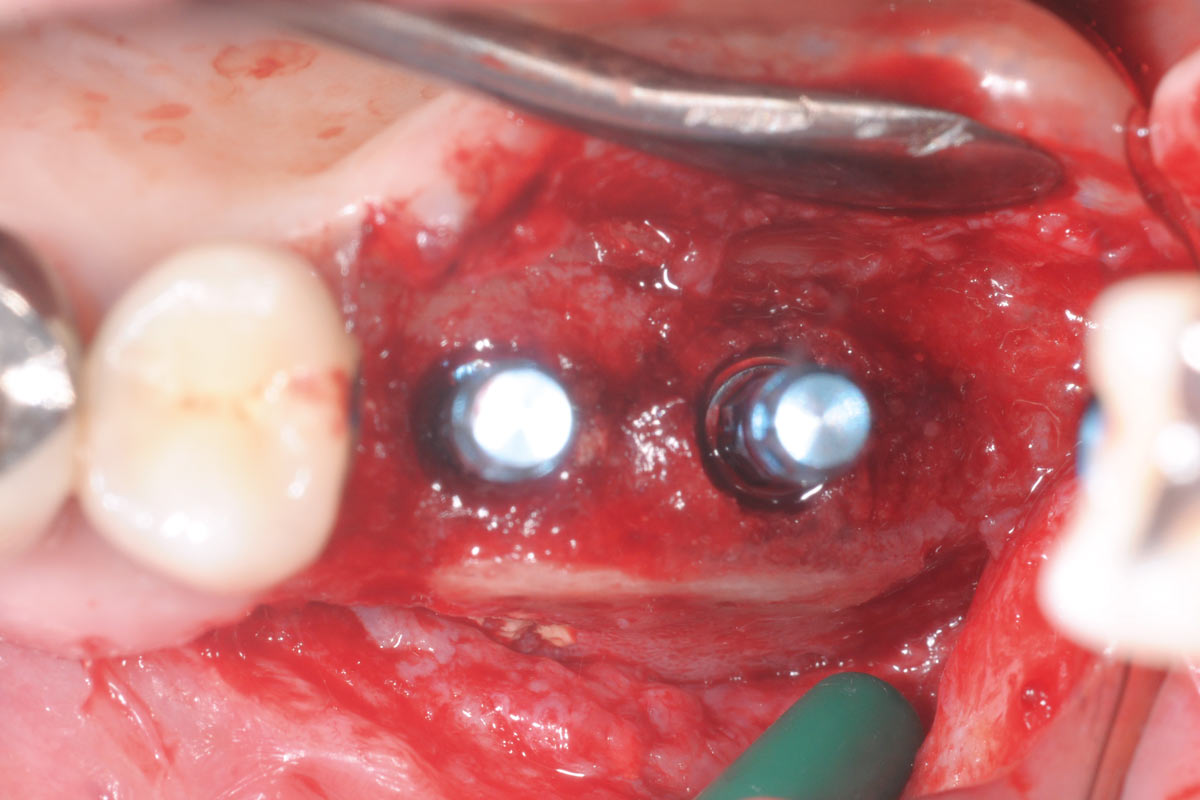

10/15 - Insertion of two Straumann Bone Level Tapered implants 4.8, 10 mm, lateral viewTreatment of a combined horizontal and vertical bone defect in the maxilla with maxgraft® cortico in the allogenic shell technique - Dr. R. Würdinger

11/15 - Occlusal viewTreatment of a combined horizontal and vertical bone defect in the maxilla with maxgraft® cortico in the allogenic shell technique - Dr. R. Würdinger